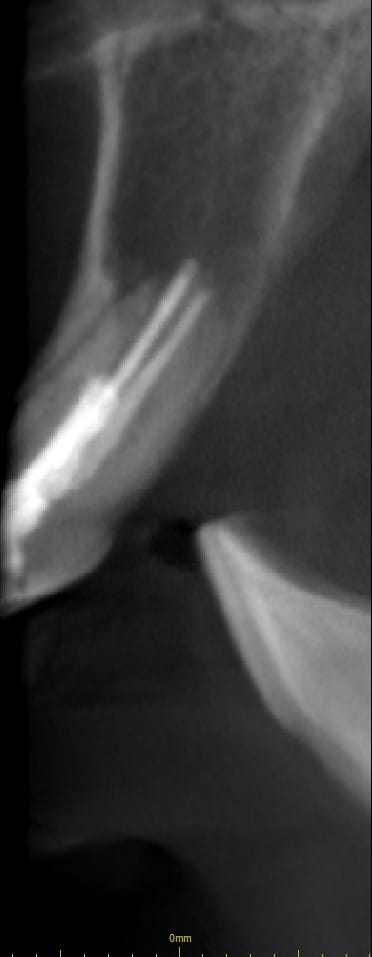

Bal oldalon egy hagyományos gyökérkezelés eredménye látható, míg jobbra ugyanazon fog mikroszkópos módszerrel végzett helyreállítása

Épp ezért a konzultáció során rendkívül alapos CT elemzést végzünk, majd olyan átgondolt, minden részletre kidolgozott kezelési tervet készítünk, melyben igyekszünk minden lehetőséget számításba venni.